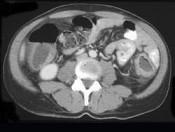

问题 女,40岁,腹痛、腹泻、脓血便、里急后重,结合图像,选择最可能诊断 ( )

选项 A.假膜性肠炎 B.结肠克罗恩病 C.结肠结核 D.慢性溃疡性肠炎 E.结肠淋巴瘤

答案 D